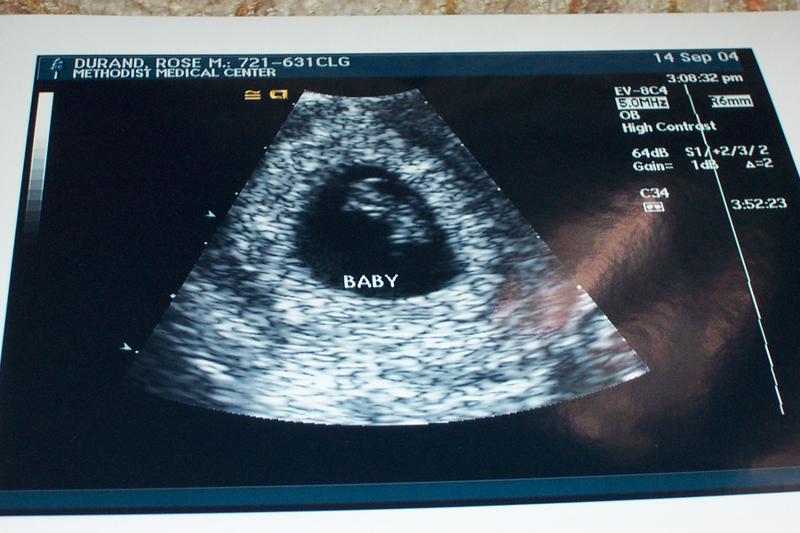

8 Week Ultrasound